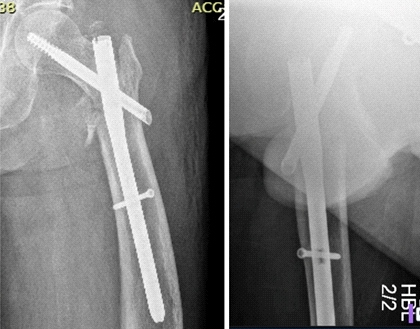

术后X线片

螺钉取出后的X线片显示骨折不愈合。

返修手术前规划:髋关节置换。